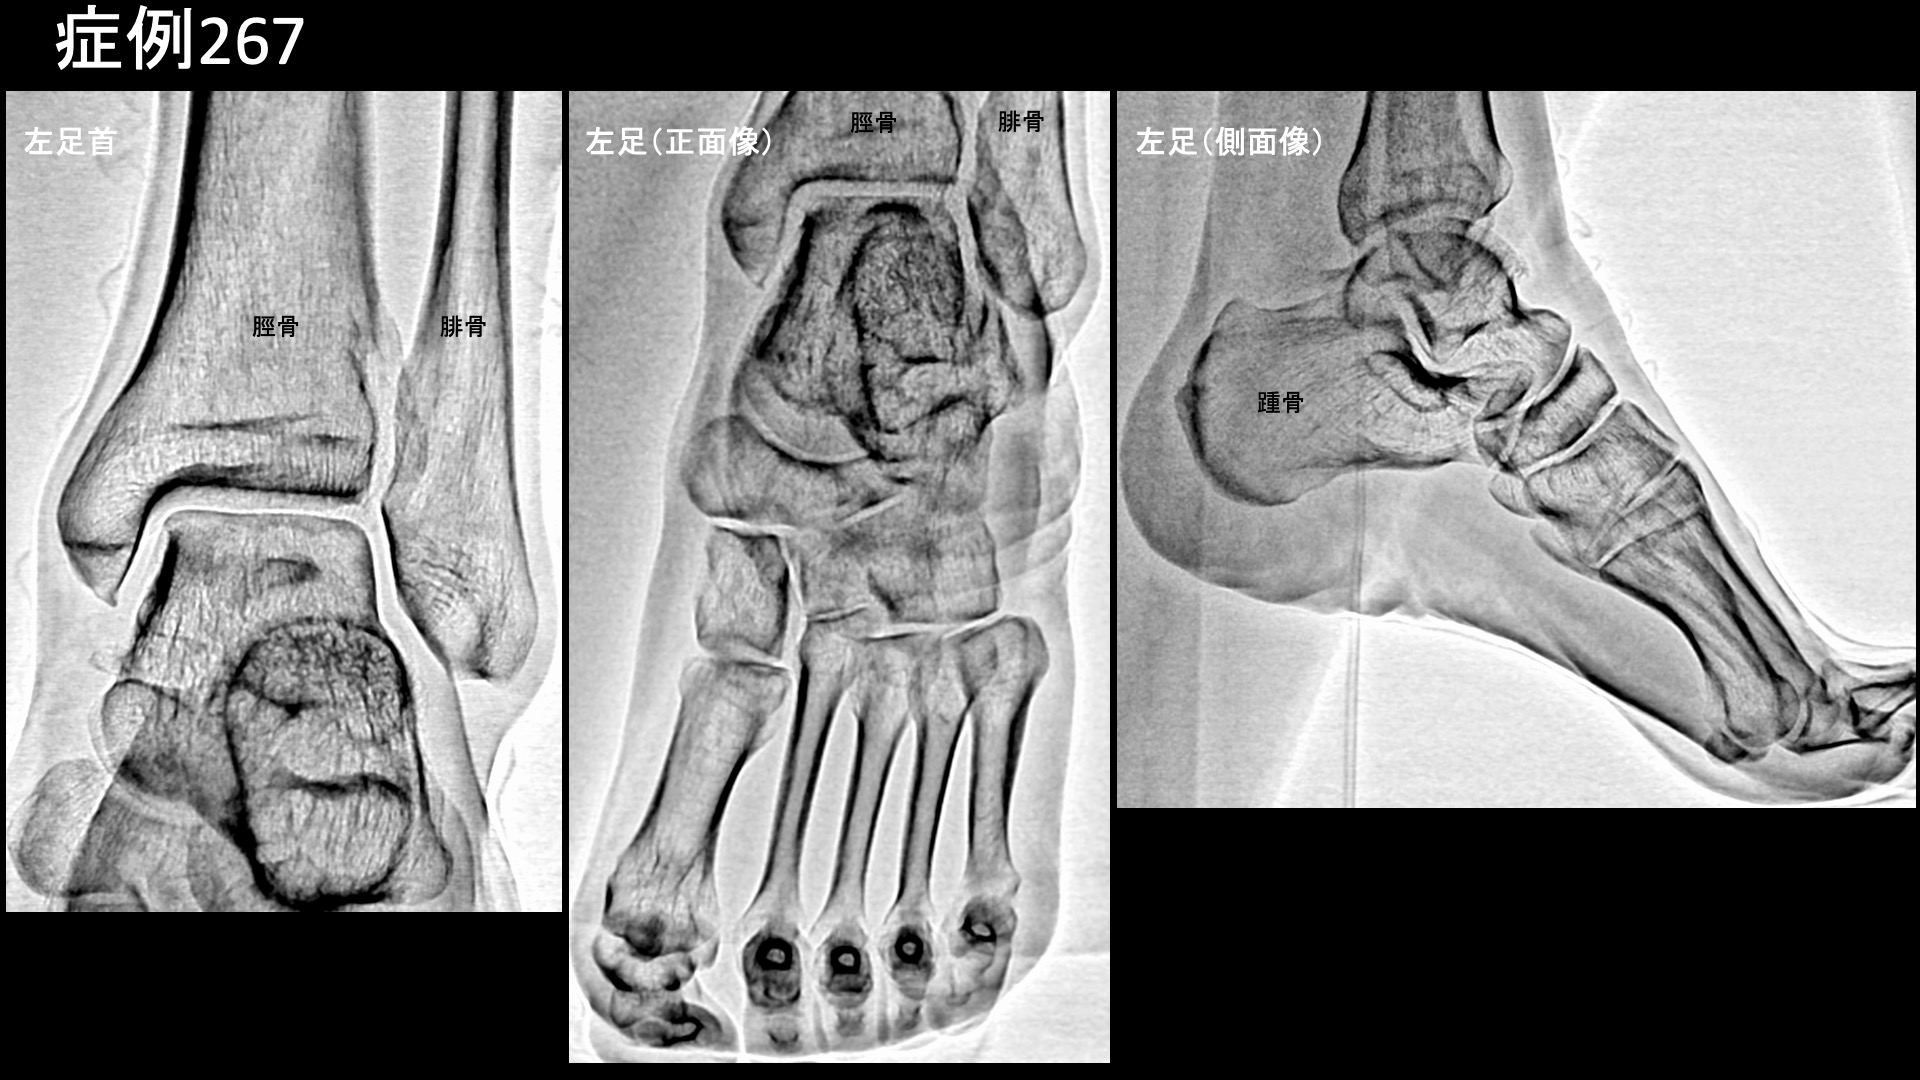

足:アキレス腱炎、足底筋膜炎、踵骨棘など 【50代:男性】足首の外側(外くるぶし)が痛い、腓骨筋腱炎に対するモヤモヤ血管治療(腓骨筋腱炎、腱付着部症) 2026.03.03 鴨井院長による動画解説 受診までの経過 2ヶ月前から左足首に違和感がありましたが、少し痛みも感じてはいたものの放置していました。徐々に悪化し、自転車に乗るとしばらくして痛むのと、ウォーキングマシンでも負荷を上げると10分程度で痛み、ついには日常生活でも支障をきたすようになりました。整形外科でレントゲンを撮りましたが、特に異常は指摘されず保存的治療方針でサポーターを処方されました。良くなっていかないため、当院を受診されました。 診察時の所見 レントゲンでは、脛骨遠位の骨棘など軽度の変形性変化を認めました。左足首の外踝近傍に限局性の圧痛を認めましたが、エコーでは同部位に一致して血流信号の増強を認めました。診断は、腓骨筋腱炎です。治療適応と判断し、モヤモヤ血管(病的新生血管)に対する運動器カテーテル治療(微細動脈塞栓術)を受けていただきました。 治療の所見 血管造影を行うと、画像上モヤモヤ血管はそれほど目立ちませんでしたが、通常どおり治療を行い終了しました。足関節(足首)においては、ある程度重症にならない限り、意外とモヤモヤ血管が目立たないことはよくありますが、治療には良く反応します。 治療後の経過 治療当日から痛みが消失しました。治療後2週間の再診時には圧痛も消失しており終診となりました。腓骨筋腱炎は腱付着部症の一種であり、モヤモヤ血管に対する微細動脈塞栓術の有効性が高い疾患の一つです。比較的早期から改善することが多いですが、まさにそうした経過でした。病態の本質は酷使(オーバーユース)による損傷ですから、今後は再発予防(適正体重の維持、靴・インソールの適正化による負担軽減、歩行・走行フォームの矯正など)に努めていただきたいと思います。 【50代:女性】1年以上悩まされた、石灰沈着性腱板炎による夜間痛を伴う右肩の痛み(石灰沈着性腱板炎、肩関節周囲炎) 前の記事 【60代:男性】諦めていた血が滴るほどの酷い痛みが劇的に改善!発症6年の頭部・顔面に生じた帯状疱疹後神経痛に対するモヤモヤ血管治療(帯状疱疹後神経痛) 次の記事